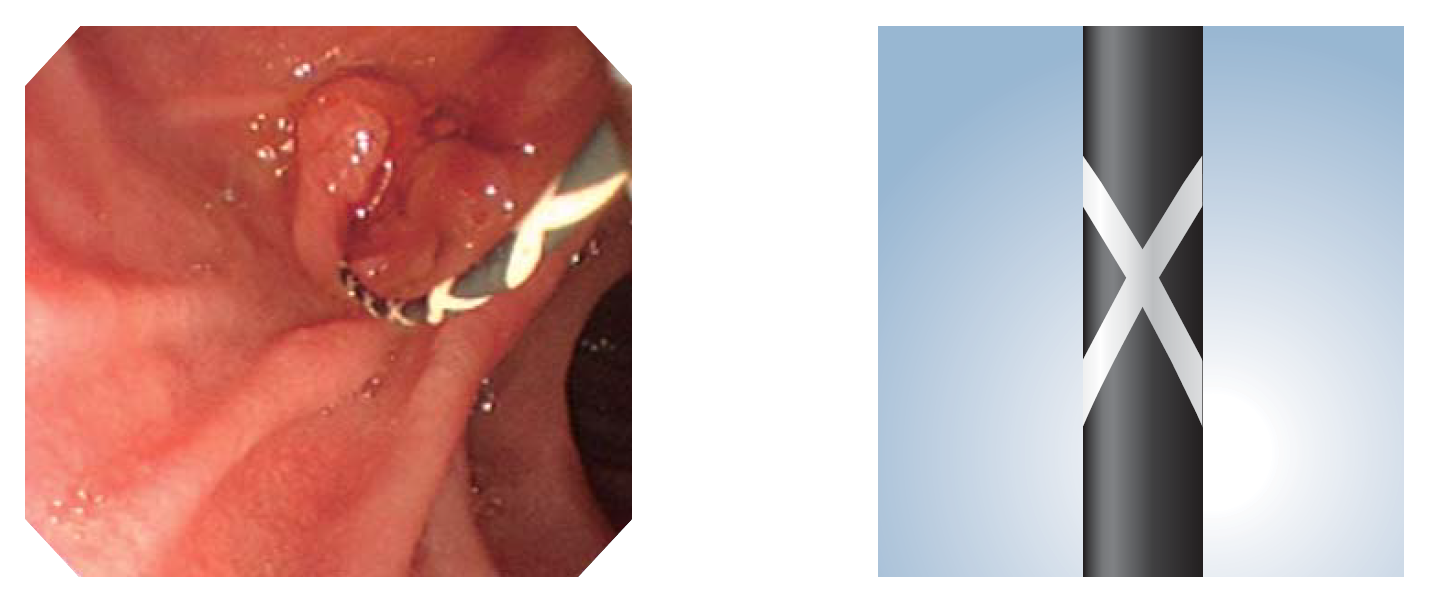

New Style Cross Marking

ガイドワイヤで初めてクロスマーキングを採用。従来のストライプタイプに比べ内視鏡下でのガイドワイヤの進退や、手元操作によるトルク伝達性の確認に効果を発揮します。